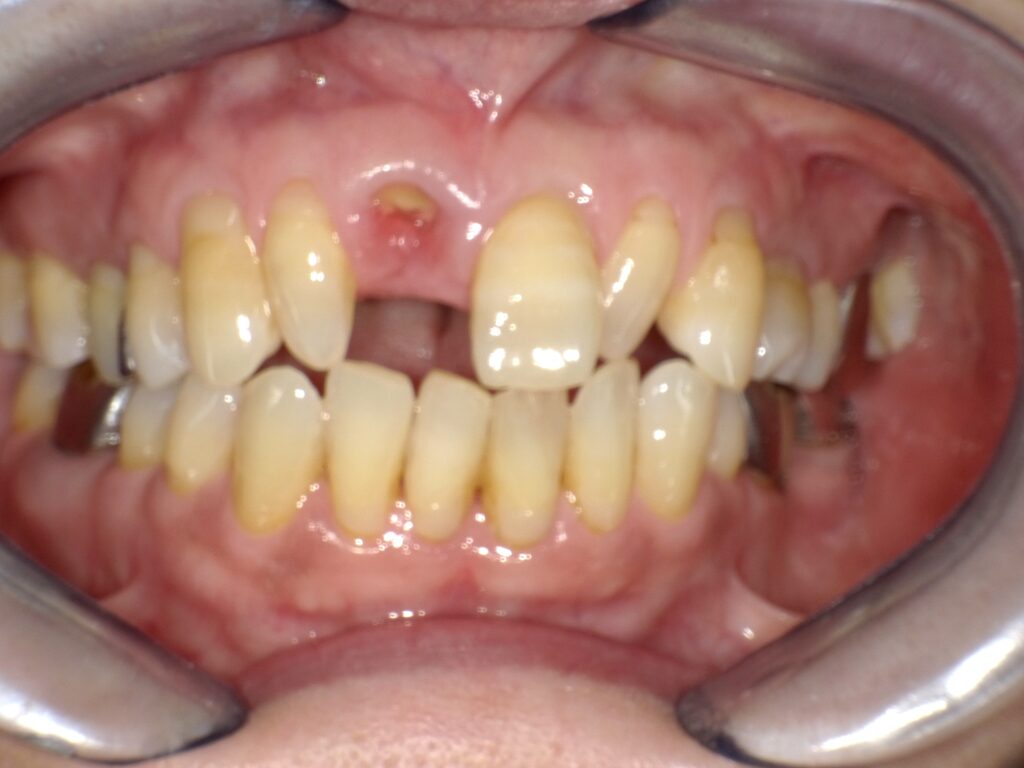

症例一覧 インプラント症例1 2024.11.25 治療内容インプラント主訴前歯部破折したためインプラント治療を行いたい費用¥671,000(1本)治療期間8ヶ月 インプラント症例2 前の記事 インビザライン症例2 次の記事